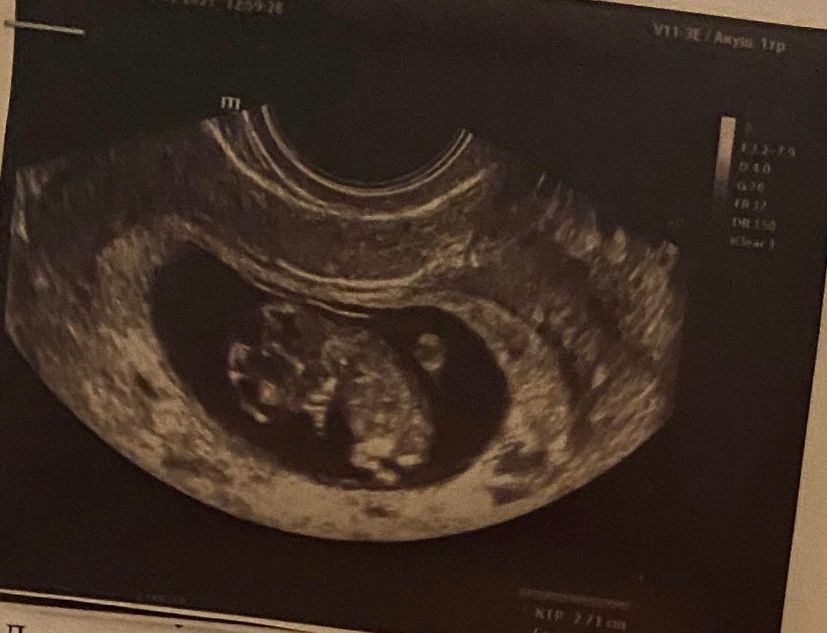

Лежит вниз головой) Нормально ли это?

На 10ой неделе наш малыш был в таком же положении))) а последние несколько узи он сидит на попе 🙈 Изображение

Настя, ну значит лежал так, у меня тоже есть фото с одного УЗИ, где он именно так лежит. Почему нет, когда еще есть возможность полежать, как хочется)) Это нормально, не переживайте.